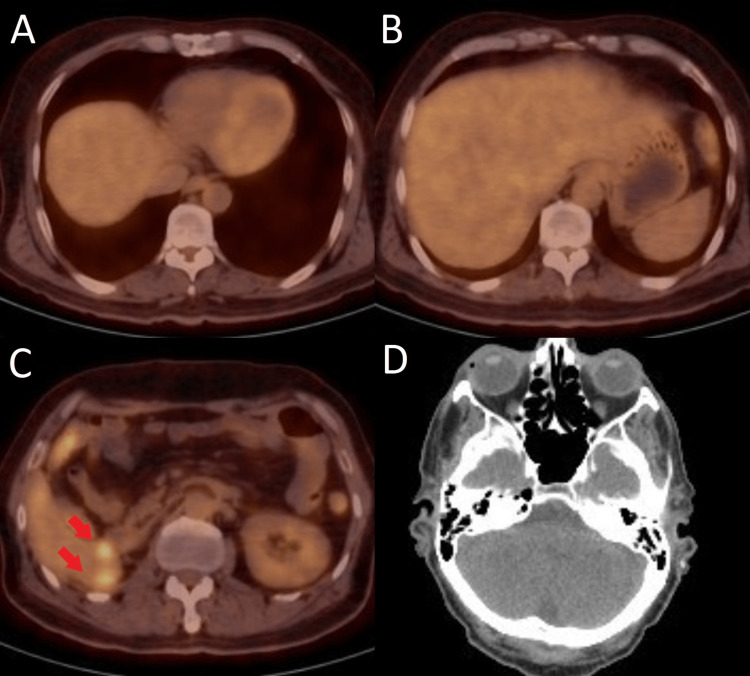

Due to the failure of first-line treatment with sunitinib, treatment was switched to nivolumab 3 mg/kg (240 mg) administered every two weeks. He also received palliative whole-brain radiation therapy (WBRT) to a total dose of 35 Gy delivered during 14 fractions. After four months of treatment with nivolumab, fluorodeoxyglucose (FDG) – positron emission tomography (PET)/CT scan was obtained and it revealed complete resolution of metastatic lesions in the brain and lungs as well as a reduction in the size and the number of lesions in the liver, without the appearance of any new lesions (Figure 3).